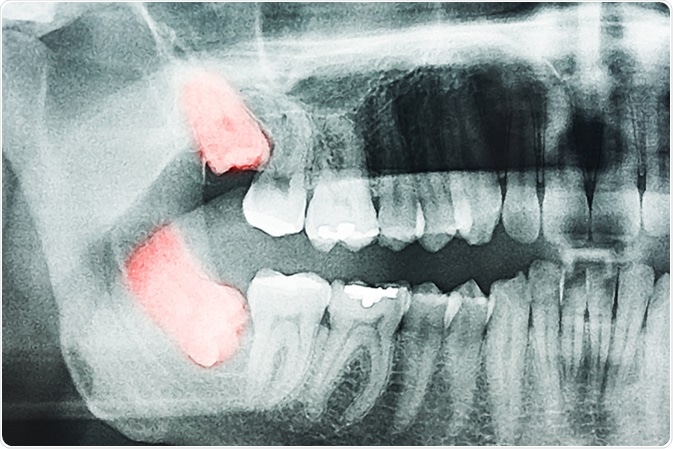

Growing Wisdom Teeth Pain On X-Ray. Image Credit: Radu Bercan / Shutterstock

On the other hand, some individuals may have impacted or embedded wisdom teeth. This type of wisdom tooth has lost its capability to erupt in the mouth and remain lodged inside the jaw bone. It may require a surgical intervention for its removal.